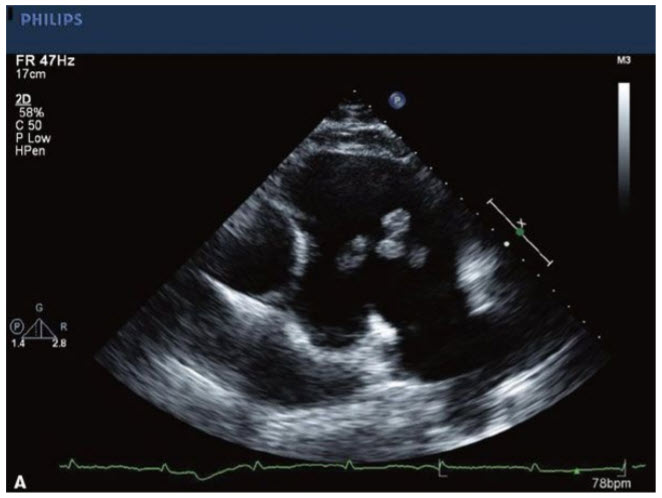

The images in Figure below A–C

belong to a 65-year-old woman with lung cancer and a central venous catheter for chemotherapy. The structure seen on these images is most likely to be:

Right atrial (RA) thrombus or thrombus on central venous catheter. The patient discussed in this question has a malignancy and is likely in a hypercoagulable state. The mass noted within the RA appears to be broad based and may be in association with her central venous catheter. In this situation, this is most likely to be an RA thrombus. The prosthetic appearing structure within the RA appears to be the central venous catheter and does not go through the tricuspid valve (TV) into the RV, and therefore is not an ICD. An RA myxoma typically has a thin stalk and is most often associated with the interatrial septum. It can be seen within the RA or left atrium (LA). Figures below A and B demonstrates a classic myxoma, one showing surgical pathology and the other showing an echo image of a myxoma. A Chiari network is a more fenestrated mobile structure seen at the junction of the vena cava and RA.